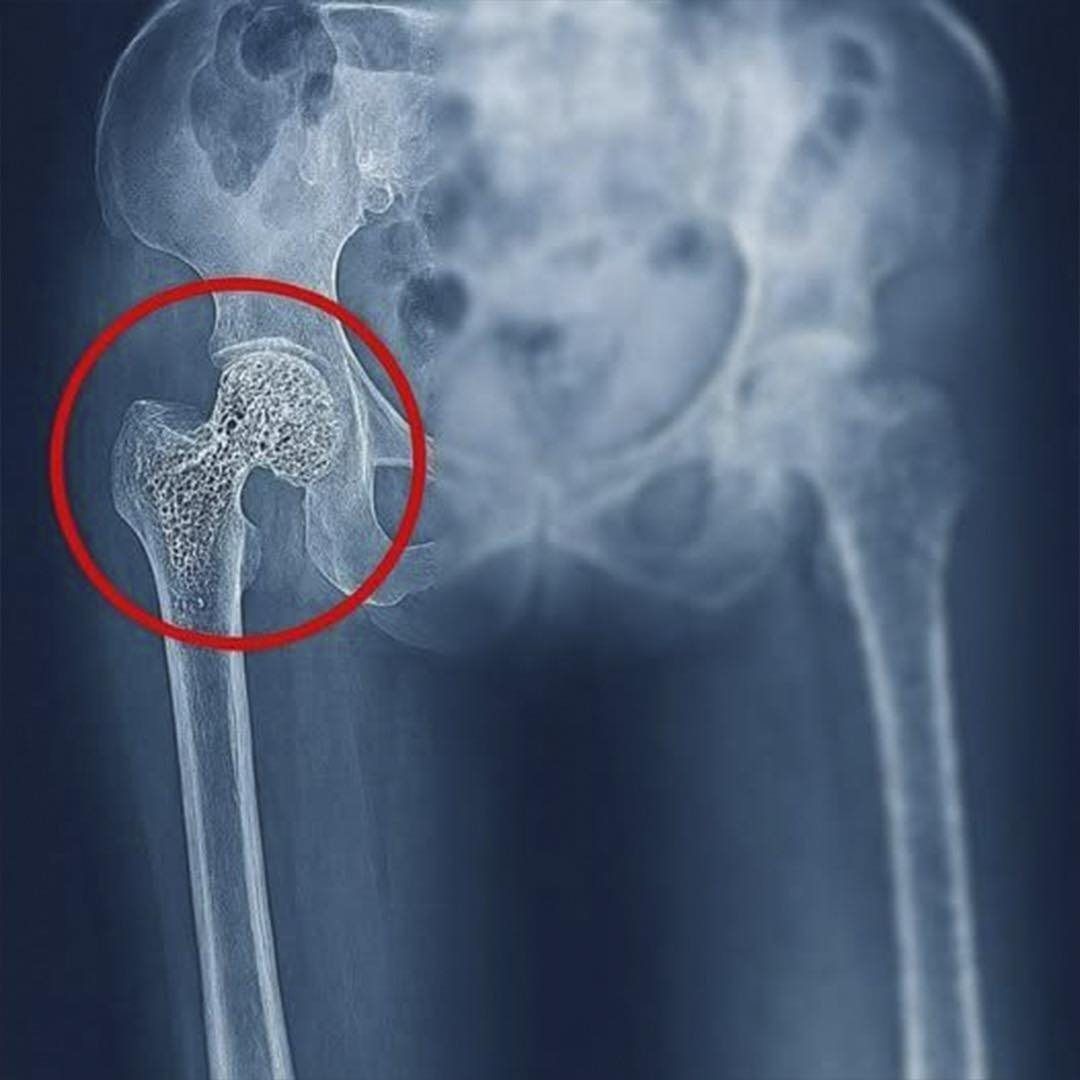

The image of a damaged hip, like the one accompanying this story, often has an immediate impact. You don’t need to be a doctor to sense that something is wrong. That red circle highlighting the hip joint is a visual warning that encapsulates a problem much larger than it appears at first glance. Behind that image lies pain, physical limitations, fear of movement, and, in many cases, a radical change in the life of the person affected.

Osteoporosis, for example, is one of the leading causes of hip fractures, especially in older adults. It is a silent disease that gradually weakens bones without obvious symptoms until a fracture occurs from minimal movement or a slight fall. In many cases, the person was unaware of their fragile bones until it was too late.

A hip fracture is not just any injury. It’s not simply a broken bone that needs rest. In most cases, it requires surgery, prolonged rehabilitation, and a recovery process that can be long and complex. Furthermore, it has a significant emotional impact: fear of falling again, loss of independence, and sometimes depression or anxiety.

But not every hip problem is a fracture. There are also conditions such as osteoarthritis, avascular necrosis, bursitis, and wear and tear. Osteoarthritis, for example, occurs when the cartilage that covers the joint deteriorates, causing pain, stiffness, and loss of mobility. It is common in people who have subjected their hips to excessive strain for years, whether from intense physical work, high-impact sports, or excess body weight.